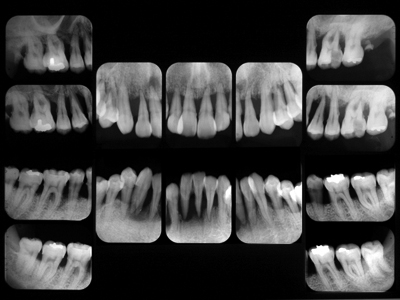

以前ご紹介した重症例の初診時の正面観とデンタルです。

歯肉の激しい腫脹疼痛発熱のため摂食困難となり入院、点滴栄養補給された方です。

'08 9主治医の紹介で当院に来院されて以来、さすがに熱心にプラークコントロールに取り組んでいただきました。'08 9~'10 2のプロービングデプスの変化です。青は6mm以上、赤はBOPを示しています。

「PD6mm以上は歯周外科」というのがEBMだそうですが、EBMってのもあまりあてにならないことがわかります。そしてこの間の上下前歯部のレントゲン像の変化です。

初診時右上1左下1はすでにに根尖をこえて骨がないようにみえますが、1年半経過し骨が戻ってきました。抜歯の前に当院に来られて本当によかった。